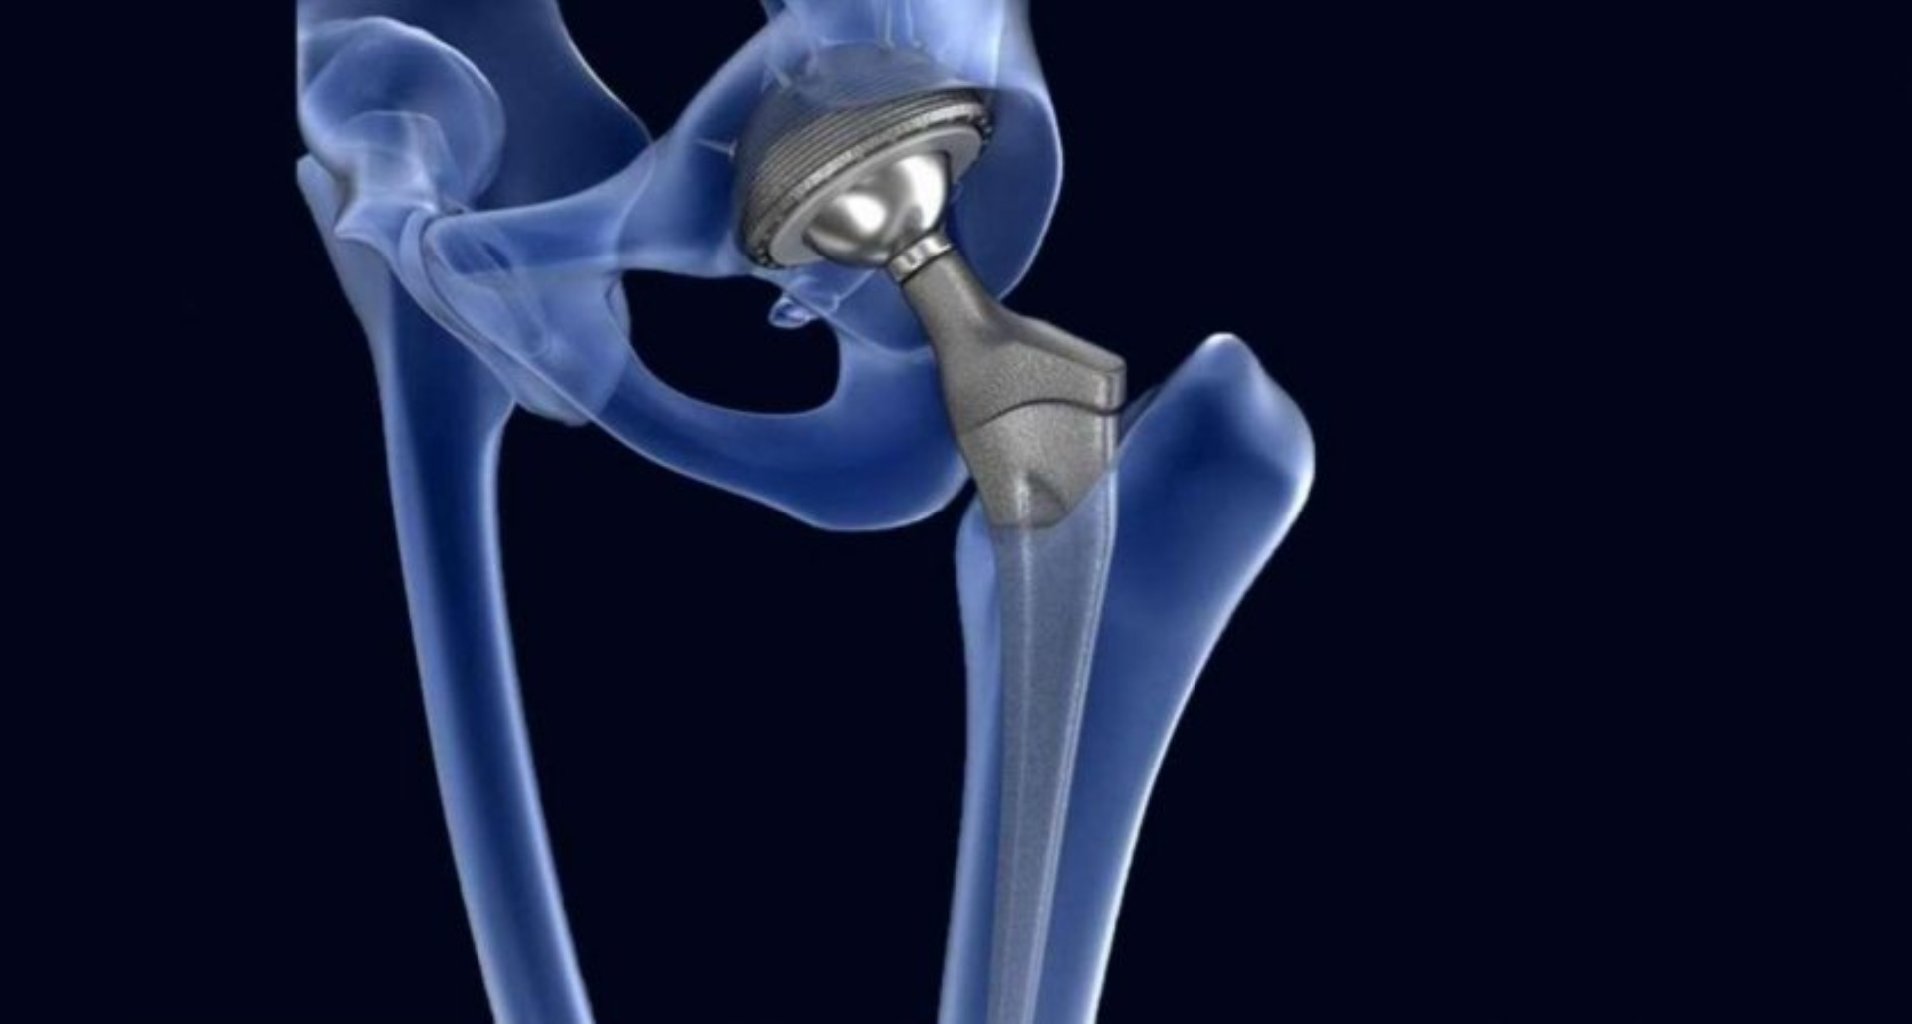

Omba protezləri titan, paslanmayan polad və ya digər davamlı materiallardan hazırlana bilər və adətə ...